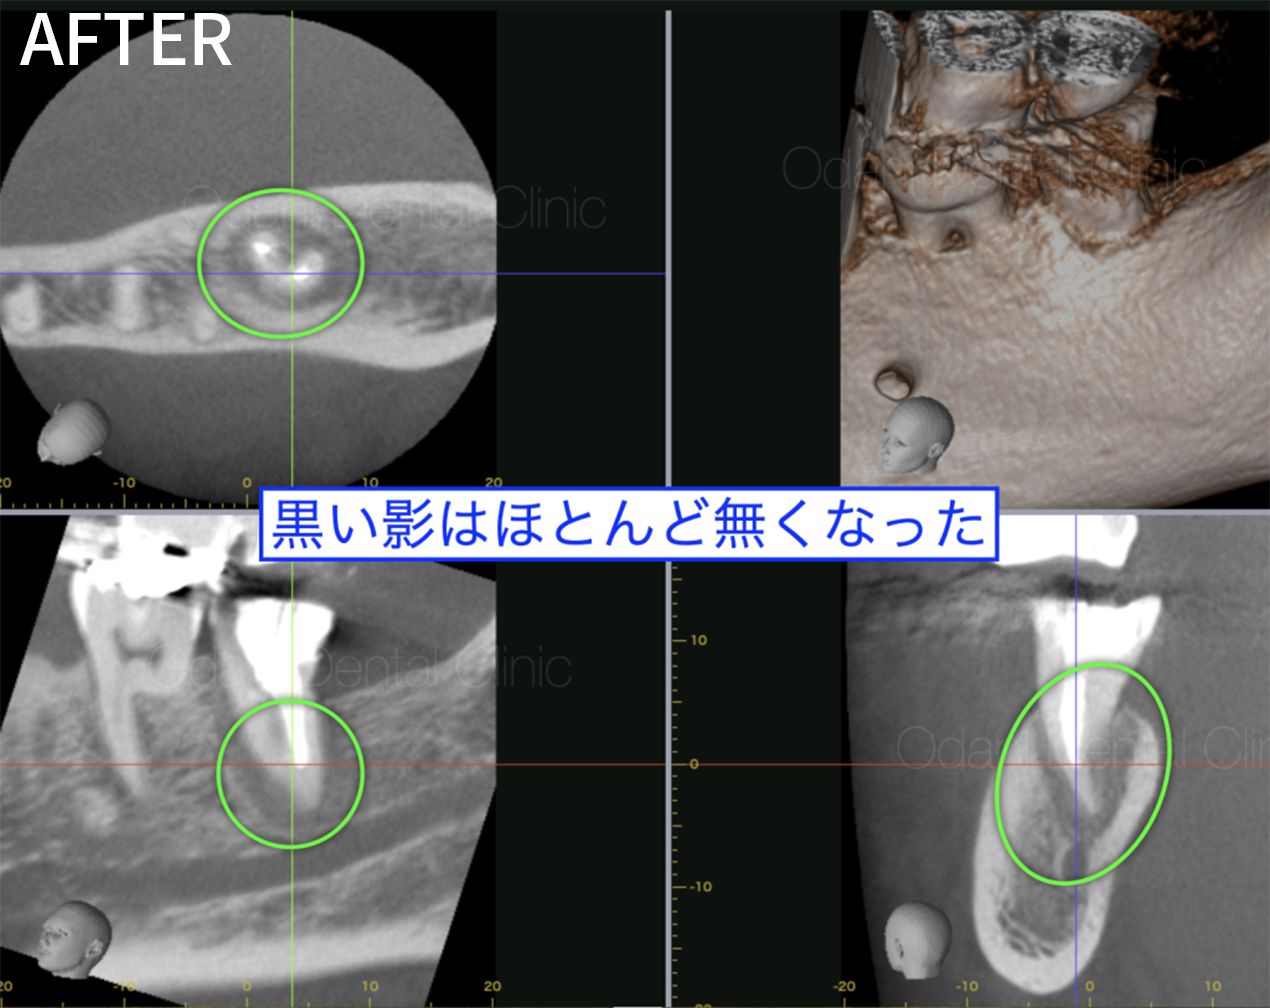

| 主訴 | 右上前歯の根の先の辺りに違和感がある |

|---|---|

| 年齢 | 20代男性 |

| 期間 |

|

| 治療部位 | 右上前歯 |

| 治療内容 |

感染根管治療(再治療) ラバーダム防湿を行い、唾液の侵入のない環境づくりを行った上で、周囲をよく消毒してから、30倍まで拡大できるマイクロスコープ下で、根管内に詰まっていた詰め物や汚れを除去後に清掃・洗浄を丁寧に行いました。洗浄には、薬剤や超音波洗浄に加え、超弾性ニッケルチタンファイルやEr:YAGレーザーも併用し、根管内の細菌除去を徹底し、根管充填(根の中の詰め物)を行いました。 |

| 治療費 |

前歯 感染根管治療(再治療) 7.7万円(税込) ※土台の補強の費用は別途となりますが、前歯の場合は状況によってかぶせ物にしない場合もあります。 |

| 起こりうるリスク |

治療後に一時的な痛みや違和感が出ることがあります。 根の病気が再発する可能性があります。 歯の変色が進んでいく可能性があります。 再発した場合、外科的な根管治療が必要になることがあります。 |